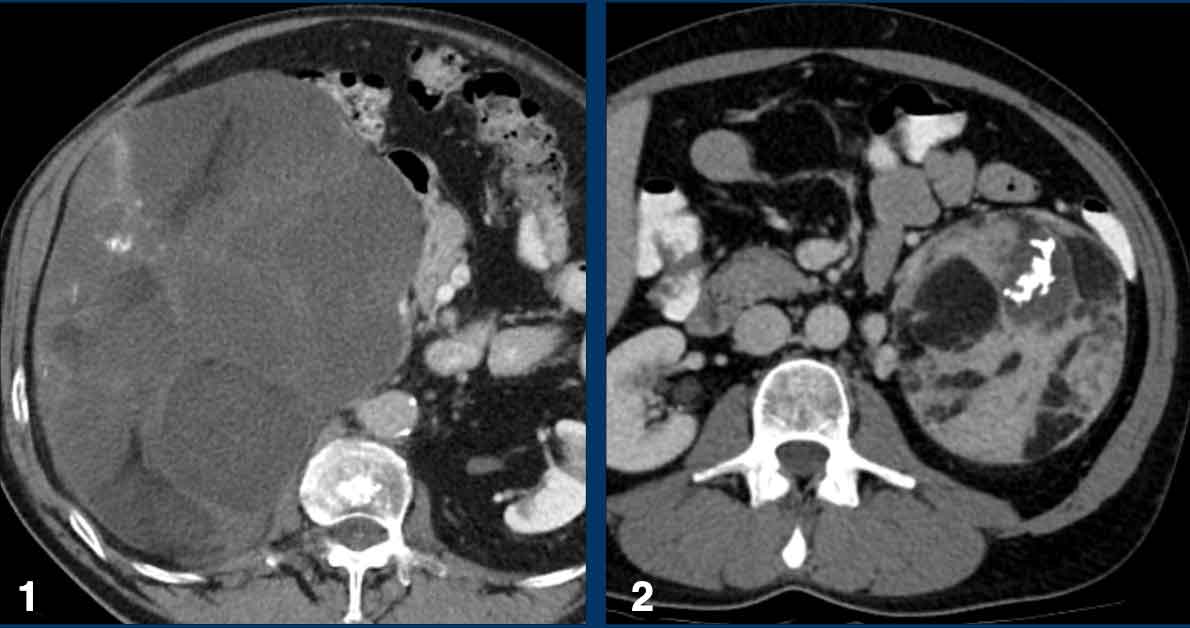

Indeterminate lesions > 4 cm

The maximum diameter of the adrenal mass is predictive of malignancy.

In particular, lesions > 4 cm are more likely to be either metastases or adrenocortical carcinomas.

Adrenal mass size is important for two more reasons.

The overall prognosis is better for small adrenocortical carcinomas and smaller tumors are easier to resect by minimally invasive surgical techniques.

Therefore, the recommendation for an indeterminate adrenal mass > 4 cm in size and no history of cancer is surgical resection -in most cases without biopsy - in order to timely treat a possible primary adrenal cortical carcinoma [3,9].

The next cases are examples of indeterminate lesions > 4 cm.

All were incidentally discovered in patients without a history of cancer.

All diagnoses were histologically proven and showed a wide variety of both benign and malignant tumors.

Adrenocortical carcinoma Adrenocortical carcinoma

The image shows a 67 mm heterogeneously enhancing relatively well defined lesion.

This proved to be an adrenocortical carcinoma, after resection.